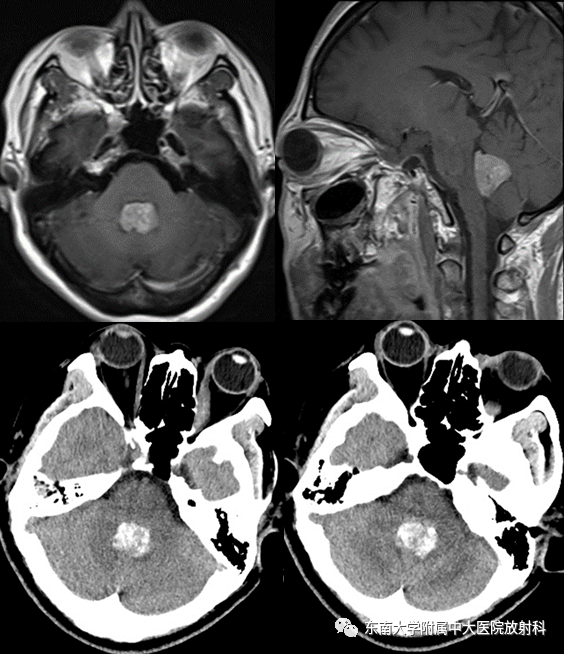

成人四脑室脉络丛乳头状瘤1例CT及MR影像

CT平扫+MR平扫及增强